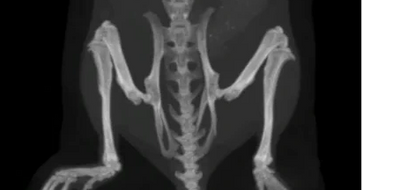

CRO osteogenesis imperfecta: Lunatum Biotech is a preclinical CRO with a special focus on CRO bone services offering well-established, valid, and reproducible in-vitro and in-vivo osteogenesis imperfecta models:

OIM mouse (B6C3Fe a/a-Col1a2oim/J), OI type III, severe; male/female; it is the most commonly used OI model and the only non-lethal murine model resembling the OI type III human disease; mutated gene: Col1a2

CRTAP mouse (B6129S7-Crtaptm1Brie/J), OI type VII, moderate; male/female; this model resembles OI that is caused by a protein envolved in collagen I processing; mutated gene: Crtap

Lunatum Biotech offers preclinical osteogenesis imperfecta research services using an array of the most widely accepted and meaningful evaluation methods for osteogenesis imperfecta, including histology, immunohistochemistry, histomorphometry, x-ray, DXA, micro-CT, biomechanical testing, ELISA, Luminex, PCR, NGS, IVIS, and more ...